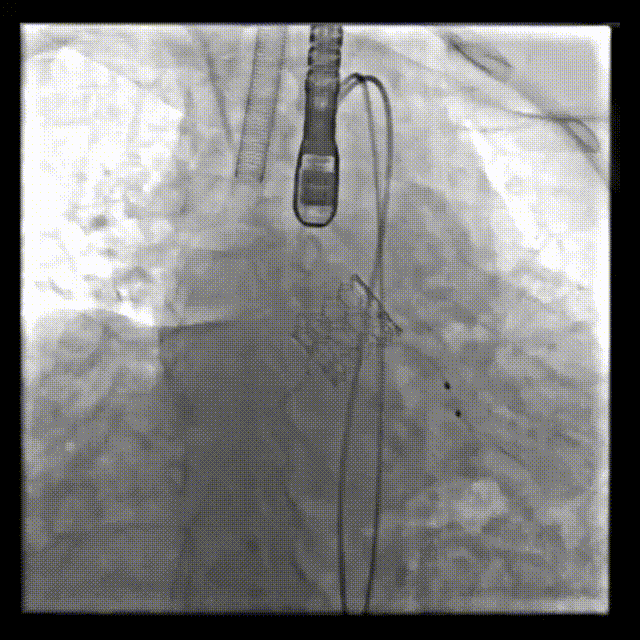

术前造影

术后造影